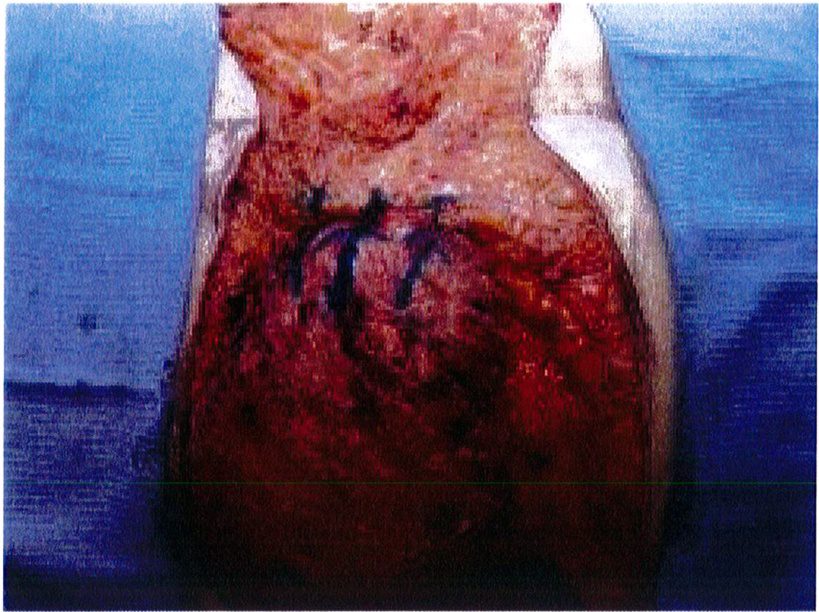

đại. Những vết sẹo này có thể được điều trị bằng các thủ thuật sửa sẹo thông thường hoặc phẫu thuật cắt bỏ. Chúng tôi chưa từng gặp trường hợp nào bị nhiễm khuẩn hoặc hoại tử mỡ sau phẫu thuật. Bệnh nhân sau phẫu thuật đa số hài lòng với kết quả của mình. Sự gia tăng thể tích mông và dựng được điểm hình chiếu là những ưu điểm độc đáo mà phương pháp này mang lại so với kỹ thuật tạo hinh vùng mông kinh điển (Hình 11-13).

Chúng tôi đã thực hiện kỹ thuật này cho hơn 40 bệnh nhân, tính tới thời điểm hiện tại. Có thể nói, với bất kỳ quy trình tạo hình cơ thể nào, tình trạng nhão/ chùng da cũng sẽ xuất hiện sau một thời gian nhất định. Tuy nhiên, trong kỹ thuật này, điểm hình chiếu và gò mông được tạo ra vẫn đươc duy trì theo thời gian. Biển chứng thường gặp nhất là tách vết mổ và sẹo phì

Hình. 11. (A, B) Bệnh nhân nữ 59 tuổi với vùng da mông chùng và xệ. (C,D) Hai năm sau phẫu thuật tạo hình thành bụng và tạo hình mông bằng phương pháp purse-string.Bênh nhân này bị tách vết mổ, sau đó đã đươc điều tri liền seo